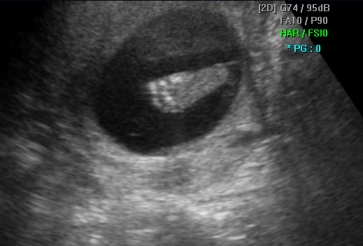

Ембрионот во најраните фази на бременоста